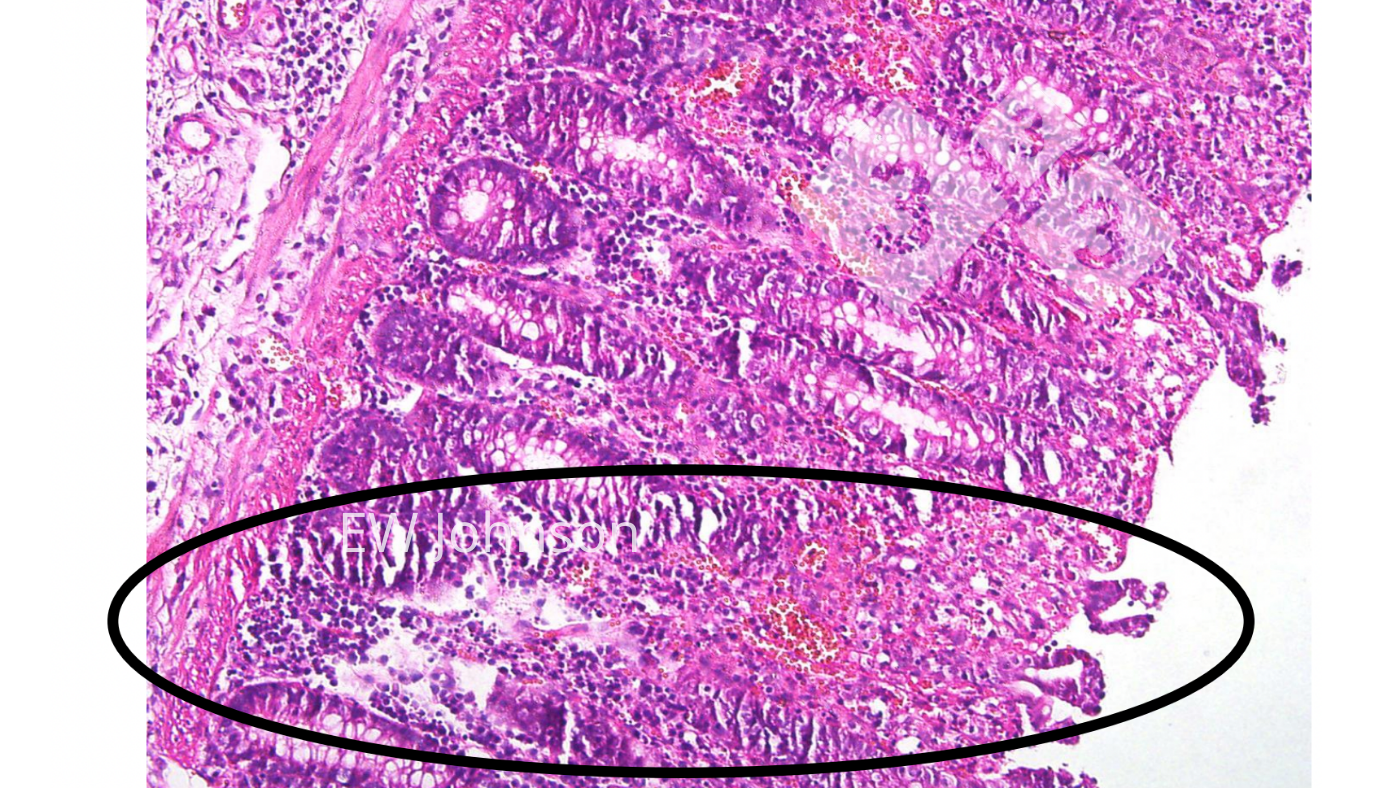

En el examen histopatológico se observa una vasculitis generalizada con infarto, hemorragia y trombosis en múltiples órganos, particularmente el pulmón, bazo, linfonodos, riñones, cerebro e intestino. Hay una destrucción linfoide masiva en los linfonodos y el bazo, y vacuolización de los macrófagos alveolares. Es frecuente la necrosis y la ulceración del epitelio del colon (foto 4).

El uso de la histopatología para verificar las lesiones crónicas típicas de la vacuna con genes deleteados puede ser muy útil. Los cerdos que han recibido dichas vacunas de PPA suelen presentar lesiones vasculares fibrosantes y cicatrizantes crónicas activas que incluyen trombos e infartos en el intestino, el hígado, los tejidos linfoides, el corazón y los riñones. Los linfonodos pueden tener áreas hemorrágicas, con necrosis y destrucción linfocitaria y zonas con fibrosis y cicatrización. Los reproductores vacunados pueden presentar grandes zonas de necrosis pulmonar y fibrosis que a menudo se confunden con App crónica. Es posible que el virus de la vacuna no mate al cerdo, pero el cerdo a menudo no puede eliminar el virus de la vacuna.